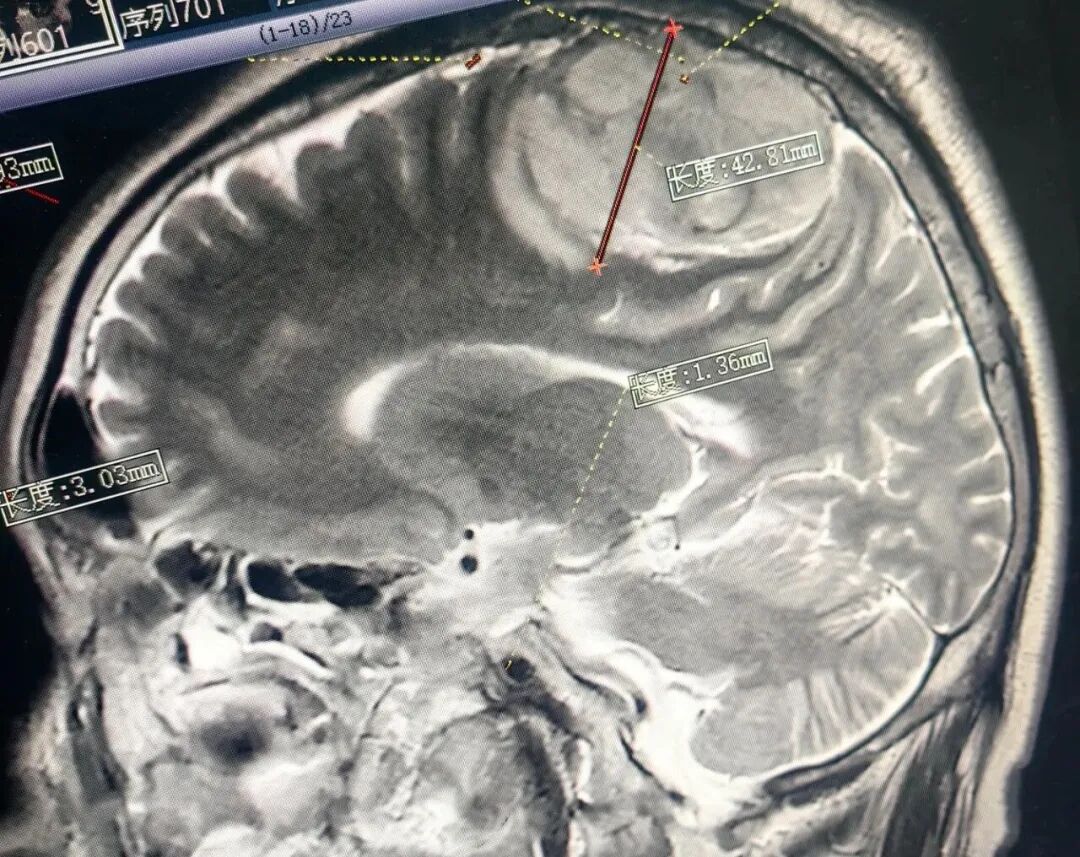

患者术前头部影像

李先生10年来常出现头昏头痛,近段时间突发右侧肢体无力伴间隙性肢体抽搐,日常生活受到严重影响。在家属的陪伴下,他来到恩阳区人民医院就诊。颅脑磁共振检查结果提示:患者左侧顶部有一个巨大脑肿瘤,大小约5.9x4.7X4.0cm。面对这一复杂病例,医院立即组织多学科讨论,手术团队综合患者情况,最终决定为患者实施脑肿瘤切除术